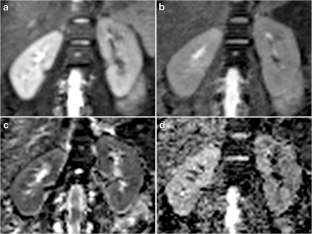

Fig. 3